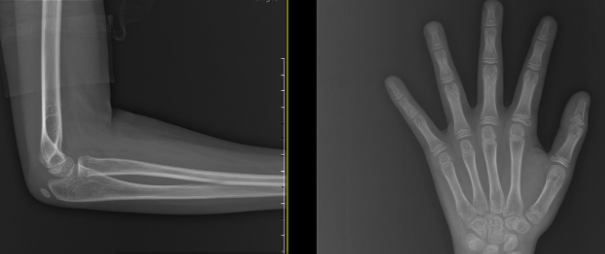

뼈나이 10세 4개월로 실제 나이보다 1년 9개월 빠릅니다.

뼈나이는 11세 정도로 잘 억제되고 있었습니다.